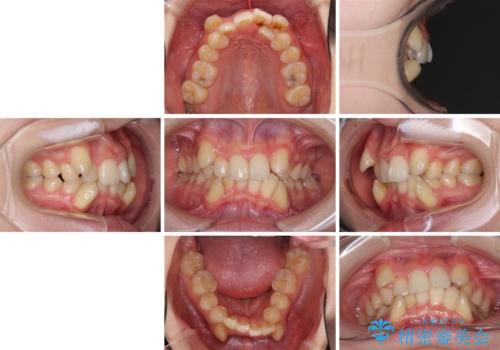

- 上下の八重歯や乱杭歯を気にして来院され患者様です。

スペースを確保するため、上下左右の第一小臼歯を抜歯し、ワイヤー装置に矯正することとしました。

結婚式の予定があったため、まずは前歯をきれいに整えるようにしました。

結婚式の時には一時的に前歯の装置を外し、口元を気にせず笑える結婚式を迎えることができました。

その後スペースを閉じるために時間を要しましたが、満足のいく仕上がりとなりました。